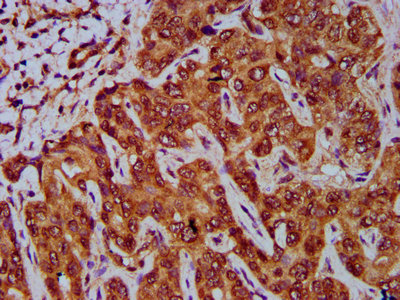

IHC image of CSB-PA009584LA01HU diluted at 1:400 and staining in paraffin-embedded human liver cancer performed on a Leica BondTM system. After dewaxing and hydration, antigen retrieval was mediated by high pressure in a citrate buffer (pH 6.0). Section was blocked with 10% normal goat serum 30min at RT. Then primary antibody (1% BSA) was incubated at 4°C overnight. The primary is detected by a biotinylated secondary antibody and visualized using an HRP conjugated SP system.